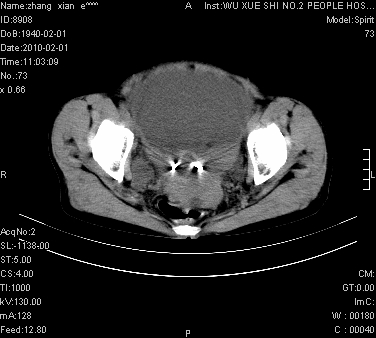

标题: CT24434:70岁 女 腹胀,腹水原因待查 [打印本页]

标题: CT24434:70岁 女 腹胀,腹水原因待查

大量腹水,脾脏囊性占位,子宫颈占位,右侧腹股沟淋巴结肿大,建议+c,先查妇科。

腹盆腔大量积液,子宫增大,子宫颈增大外形不规则,内见低密度影,膀胱后壁显示不清,右腹股沟肿大淋巴结,脾脏囊性占位,子宫颈占位,子宫颈癌?建议增强。

腹盆腔大量积液,子宫增大,子宫颈增大外形不规则,内见低密度影,膀胱后壁显示不清,右腹股沟肿大淋巴结,脾脏囊性占位,子宫颈占位,子宫颈癌?建议增强。支持!